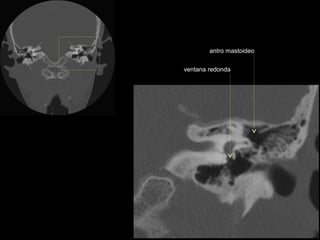

antro mastoideo

celdillas retrolaberínticas

ventana redonda